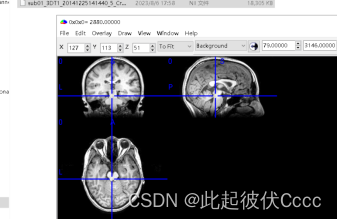

其中sub01_3DT1_20141225141440_5_Crop_1.nii文件便是我们后期需要处理的.nii文件,用mricron软件查看图像如下图所示: